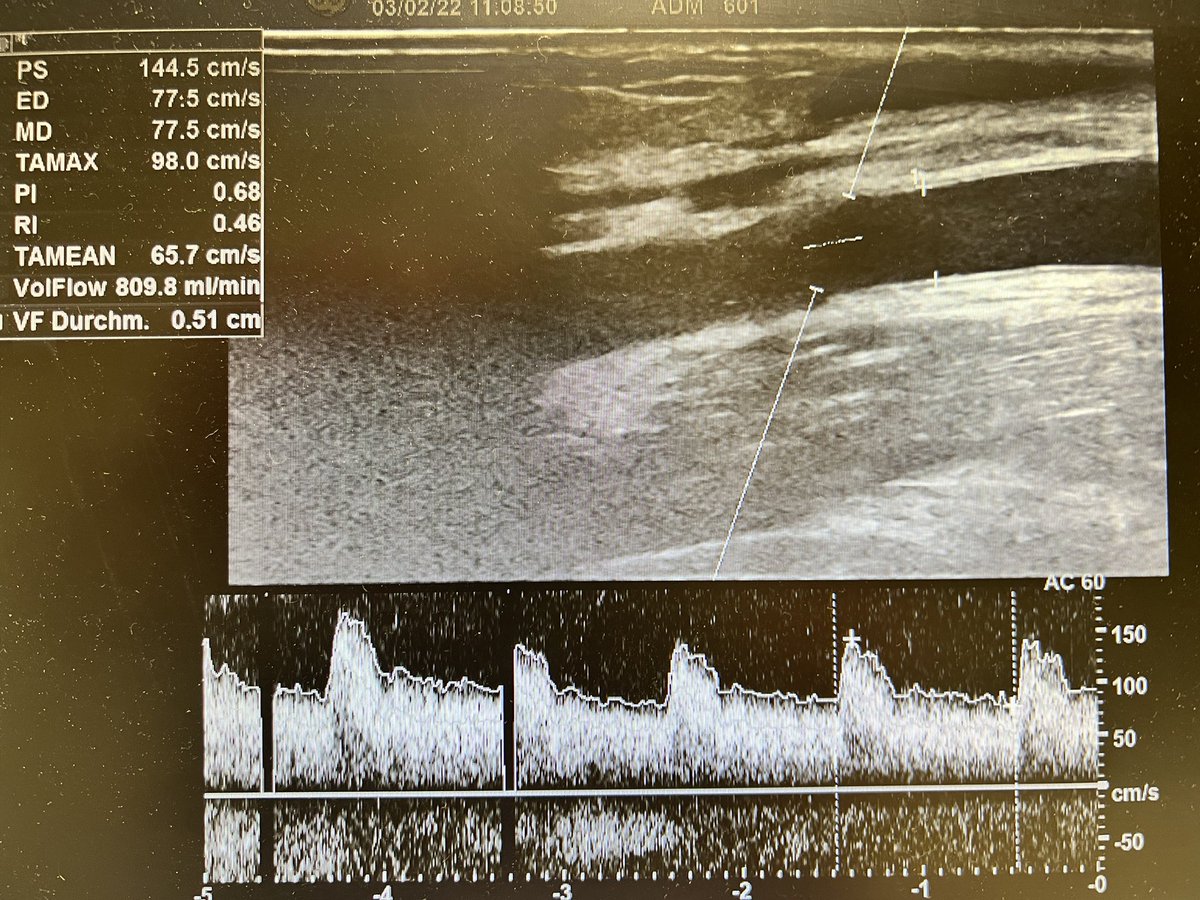

Brachial artery and mid level forearm cephalic vein before (fig 1-2) and exactly 2 days!!!! after (fig 3-4) the creation of a

#VasQ#RCAVF in a#CKD patient@wasse_m@jimbog_76@OBaumgaertner_#VascularAccessCenter#Hamburg#Barmbek#LaminateMedicalpic.twitter.com/0aX0710Wnu